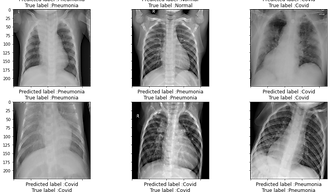

Pre-trained Deep Learning Models for Coronavirus (Covid-19) Prediction from Chest X-ray images

Real-Time Data Streaming with Apache Kafka and AI for Health Risk prediction of ECG signals

8. BADAWI, A., & Elgazzar, K. (2021). Detecting coronavirus from chest X-rays using transfer learning. Covid, 1(1), 403-415.